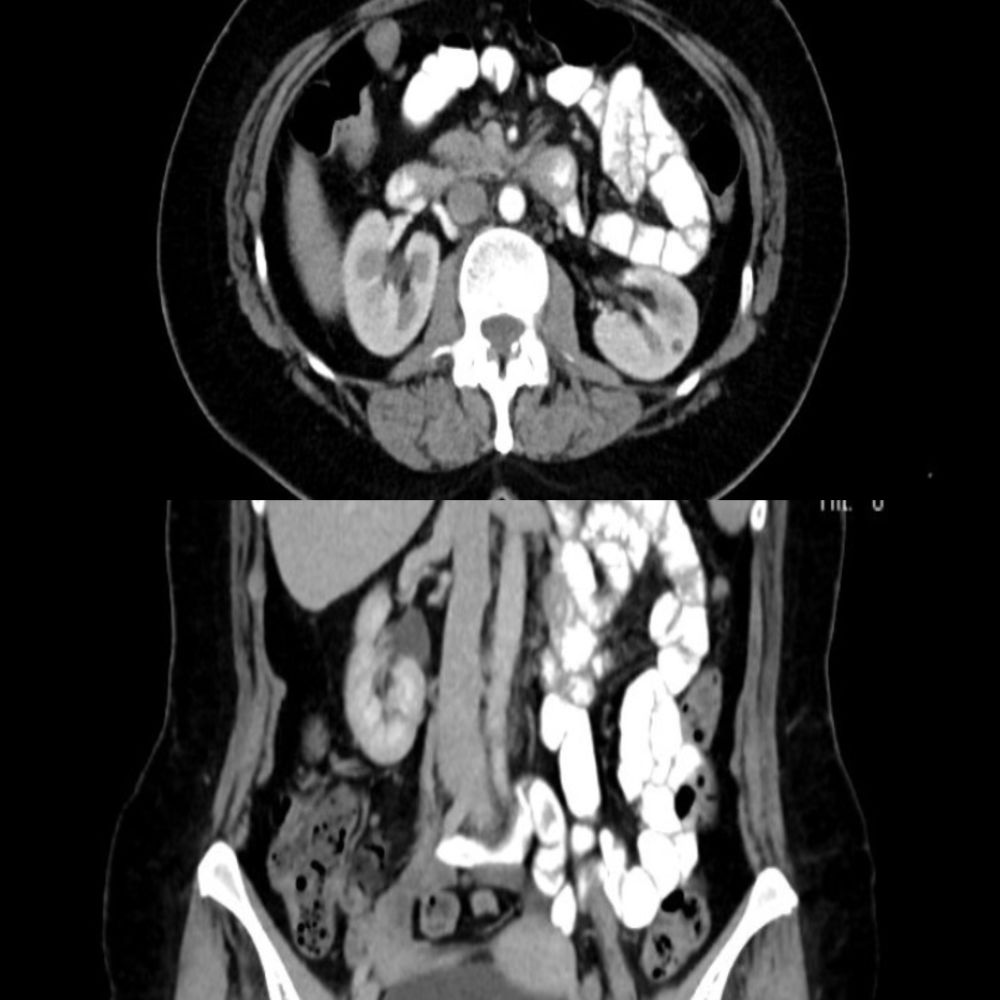

Kliniğimizde yapılan detaylı fizik muayene ve geçmiş radyolojik görüntülerin (BT) geriye dönük titizlikle incelenmesi sonucunda, 11. kaburganın önünde yerleşmiş 15×10 mm boyutlarında küçük, iyi huylu bir düz kas tümörü (leiomyoma) tespit edildi. Bu küçük tümör interkostal sinire baskı yaparak hastanın 3 yıl boyunca “nöropatik ağrı” çekmesine neden olmuştu.

Gerçekleştirdiğimiz cerrahi operasyonla, tümör ve komşu kaburga segmenti tamamen temizlendi.

Patolojik inceleme sonucunda tümörün iyi huylu olduğu (leiomyoma) kesinleşti. Ameliyattan hemen bir gün sonra taburcu olan hastamızın, 6 aylık takibinde tüm ağrılarının tamamen geçtiği ve sağlığına kavuştuğu gözlemlendi.